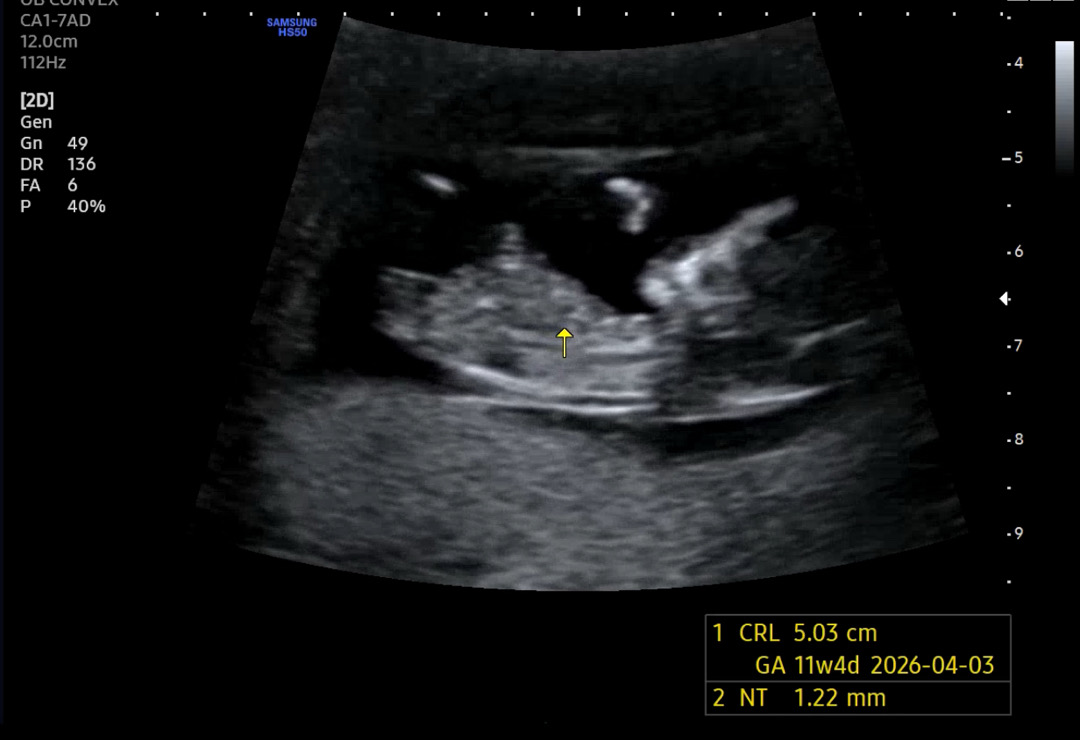

각도법 봐주세요오!!

11주라 오류가 많다곤 하지만 여러분들의 의견이 궁금합미다!! 담주에정밀 초음파 보러가는데 궁금해죽겠네요🥺